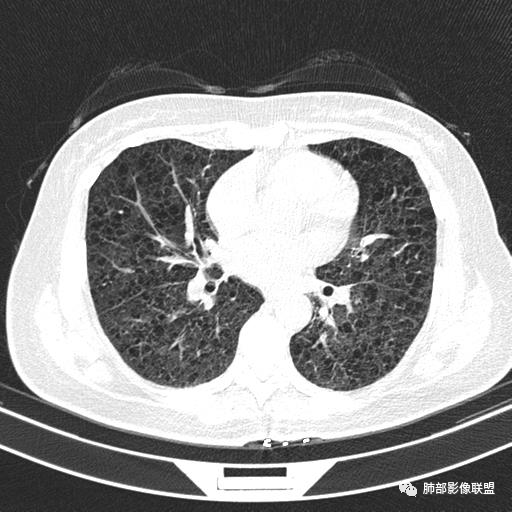

双肺弥漫囊腔,累及肋膈角,囊腔形态相对规则单一。

CT平扫示双肺弥漫分布大小不等囊状薄壁透光区,无内、中、外带分布差异,间质稍示增厚。拟LAM

中年女性育龄期妇女,咳嗽气喘,无吸烟史,有苯吸入史。影像:双肺弥漫均匀小囊腔,无明显分布优势,囊腔形态欠规则,壁薄,部分囊腔边缘血管征,伴双肺弥漫磨玻璃影,无结节,考虑lam,鉴别苯中毒肺损伤,囊腔多有分布优势,小叶中心分布为主,形态规整等

女,46,活动性气喘1年。苯吸入史半年。胸部CT:两肺弥漫囊腔,上至肺尖,下至肋膈角,形态类似小囊腔。考虑:LAM,鉴别LIP,BHD,PLCH等。

双肺弥漫大小不一薄壁含气囊腔,囊间肺组织正常,正常肺背景,肺尖肺底受累;青年女性,气喘,支持LAM

双肺多发大小相近的囊状影,分布趋势趋于一致,中年女性,考虑LAM。部分囊内见血管及分隔影,小叶中心性肺气肿代排

CT表现:双肺弥漫大小不等的薄壁囊腔,囊壁<2mm,外形规则,血管影多位于囊腔周围,囊腔之间肺组织正常,随着疾病进展到晚期,囊腔变大、增多,不可胜数,囊腔可融合成较大的囊,与肺气肿相似,形成间质性肺纤维化。部分病例可出现结节影。